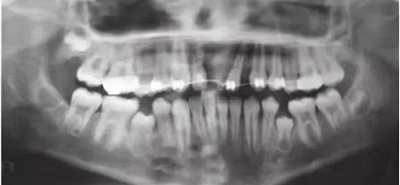

初步正畸牽引嵌入的上頜側(cè)切牙并重新獲得切牙空間。上頜側(cè)切牙的預(yù)后顯示有嚴(yán)重的牙根吸收。因此需要拔除上頜側(cè)切牙(圖3)。

圖3. 影像學(xué)顯示上頜側(cè)切牙牙根吸收